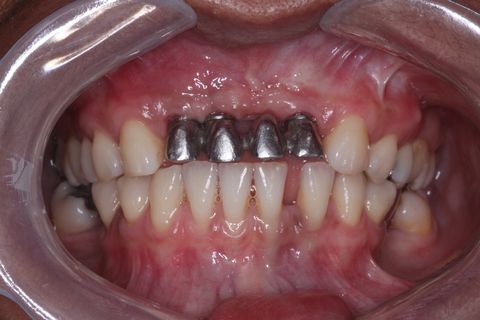

Foto Inicial. Paciente fazendo uso de Prótese Parcial removível.

Foto de frente sem a Prótese Parcial Removível

Notar defeito ósseo.